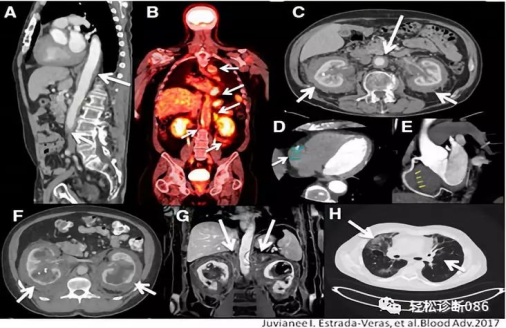

为找出病因,医生给她做了一个叫“PET-CT”的全身扫描,结果发现了重要线索:脖子至躯干区域(尤其是心脏和腹部大血管周围)存在大量异常软组织影;胳膊和腿的长骨(如大腿骨、小腿骨)两侧对称性地显示出异常信号,且这些区域的骨头硬度较正常水平有所增加。

怎么诊断这个“狡猾”的罕见病?据医生介绍,全身PET-CT扫描特别重要,能看清病变在全身哪里“作怪”。典型的骨头表现(两边长骨对称硬化)、典型的“毛状肾”、血管被“包裹”的影像,都是重要线索。最终确诊必须靠活检!取有病变的组织(如淋巴结、骨头)在显微镜下观察,看到那些特征性的泡沫细胞、巨细胞,再结合免疫组化(比如`BRAF V600E`阳性),才能拍板。目前最有效的治疗方法之一是使用特定的靶向药物治疗。

医生提醒,若遇到不明原因的发热伴随骨痛,影像学检查(如骨扫描、PET-CT)显示双侧肢体长骨对称性出现异常信号或硬化,表现为“毛状肾”或大血管被“包裹”,就要考虑ECD这一罕见病的可能性,及时进行病理活检是关键,以避免漏诊和误诊。早期诊断和早期治疗(尤其是针对BRAF V600E的靶向药物)对于改善患者预后至关重要。